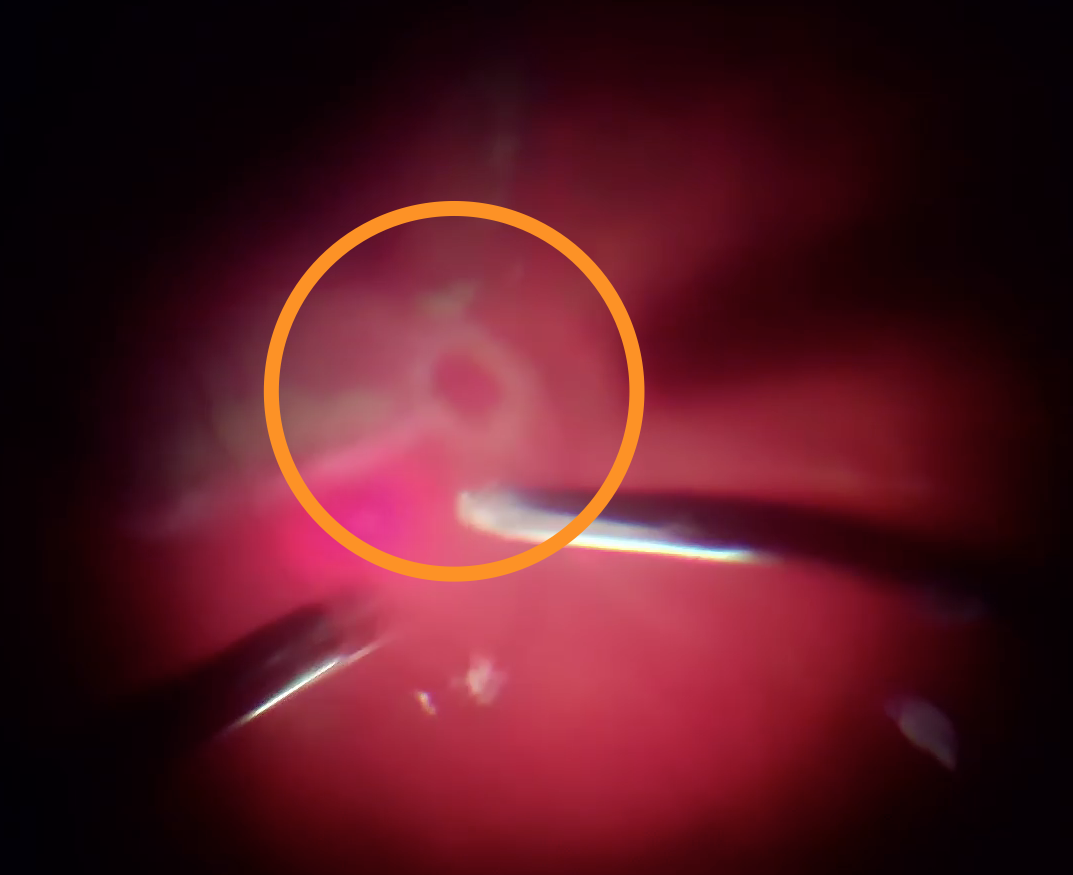

Після діатермії було виконано дренуючу ретинотомію на межі крововиливу (можна було би ще ближче до центру, але не хотілося потім виконувати лезеркоагуляцію поблизу до СНМ) та частково роздреновано субретинальній простір.

В подальшому з використанням пухиря ПФОС на сітківці та пухиря стерильного повітря під сітківкою виконано розрідження та дислокація субретинального крововиливу з аспірацією рідкого гему крізь дренуючу ретинотомію.

Під час операції вдалося відмити значну частину субретинальної крові, що дає право сподіватися на збереження макулярних функцій, разом з цим, згорток крові, що знаходився під сітківкою протягом 3 тижнів, вже почав фіброзуватися - такі тяжі видалити не вдалося. Ми розраховуємо на те, що такі тяжі розташовуються ближче до аркад, тому на фовеолярні функції впливати не повинні.